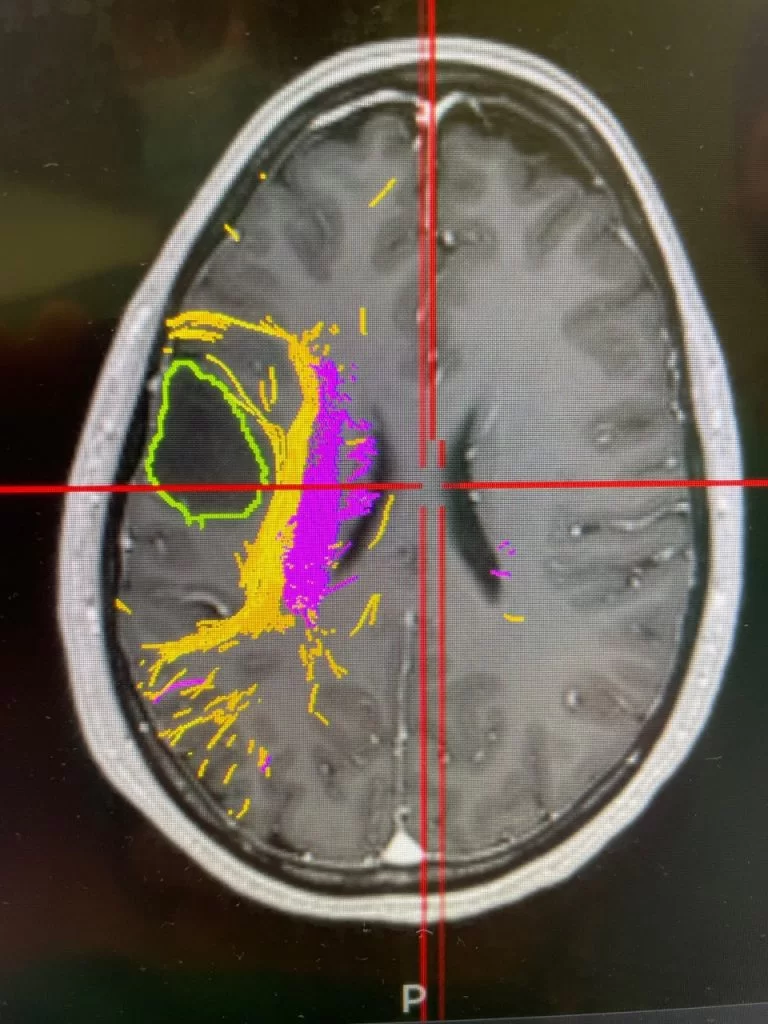

Για να πραγματοποιηθεί η επέμβαση επιστρατεύτηκαν τα πιο σύγχρονα τεχνολογικά μέσα, όπως η διεγχειρητική χαρτογράφηση του εγκεφάλου, η νευροπλοήγηση και ο διεγχειρητικός υπέρηχος, ενώ προεγχειρητικά έγινε λεπτομερής απεικονιστικός έλεγχος για να διαπιστωθεί το πού βρίσκονταν οι λειτουργικές περιοχές και τα λειτουργικά δεμάτια του εγκεφάλου και το πόσο κοντά περνούσαν από τον όγκο. Στη συνέχεια η ασθενής υπεβλήθη σε λεπτομερή νευροψυχολογικό έλεγχο, για να μελετηθεί με ακρίβεια η κατάσταση των εγκεφαλικών λειτουργιών και να προσδιοριστούν οι ερωτήσεις & οι δραστηριότητες που θα έπρεπε να απαντήσει ή να εκτελέσει κατά τη διάρκεια της επέμβασης.